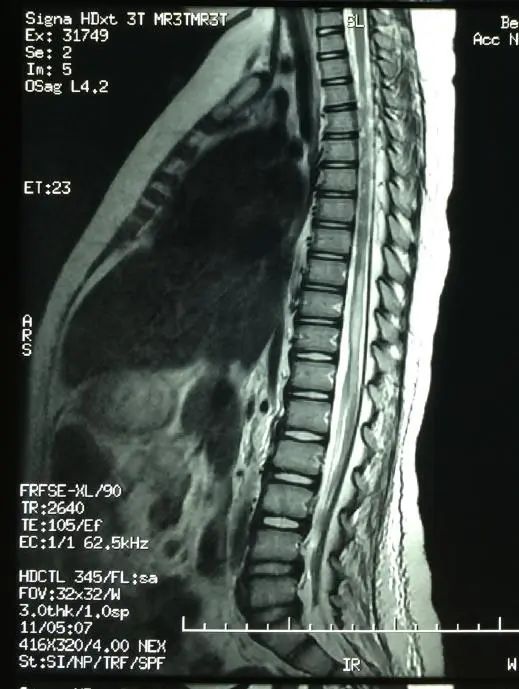

“根据MRI提示胸7~8节段脊髓肿胀坏死样异常信号影,小彩进行了多种相关检查,包括腰椎穿刺脑脊液和血液方面检测,除外了免疫性、感染性、肿瘤性等多种导致脊髓损伤的原因,最终考虑为下腰动作导致的脊髓损伤。”王三梅告诉记者,这种情况属于下腰动作引起的无骨折脱位型脊髓损伤,即在影像学检查上是脊柱无椎体骨折、脱位表现,正因为这种特点,很容易被漏诊、误诊。